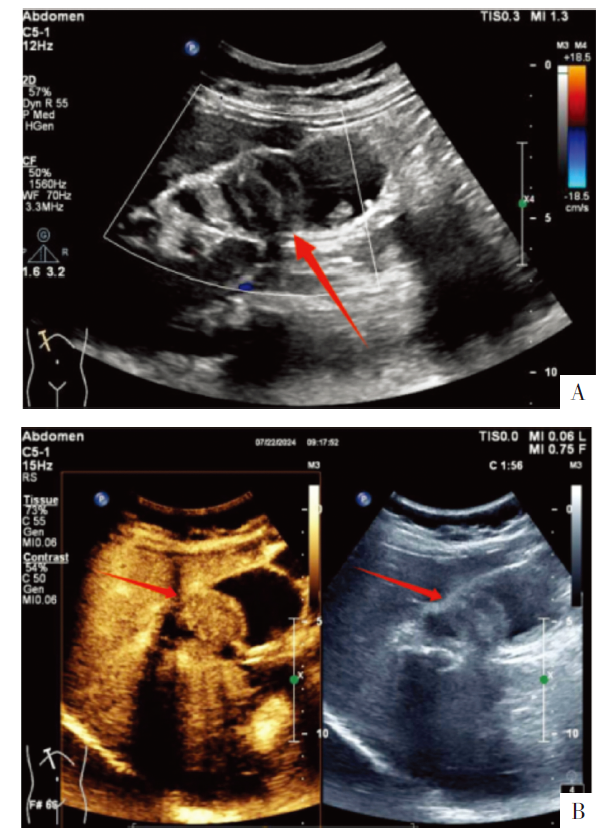

图1 胆囊病变的腹部超声影像。A图为腹部超声影像,B图中左图为超声造影影像,右图为灰阶超声影像。图中箭头示胆囊病灶。